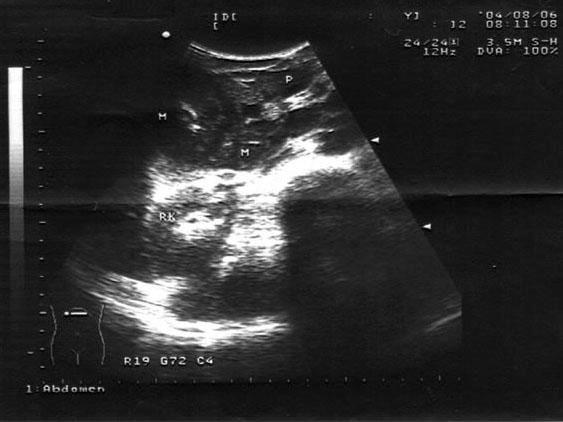

问题 男,16岁,转移性右下腹痛数小时。麦氏点压痛(+),肠鸣音减弱。结合超声声像图,诊断为?(?)

选项 A.输尿管结石 B.肠套叠 C.肠梗阻 D.急性阑尾炎 E.回盲部肿瘤

答案 D